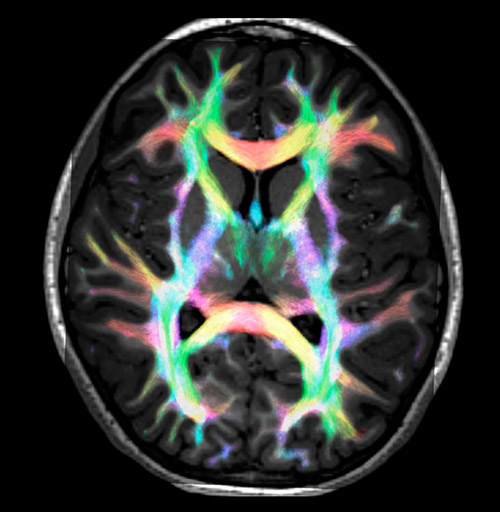

Super-resolution directionally encoded color track-density imaging overlaid on T1-weighted structural MRI.

All images were created from the same acquisition in a child using Ingenia 3.0T CX and 32-channel dS Head coil. Diffusion data was acquired at b-values 0, 500, 1000, 2000, 3000. The use of high b-values (3000 s/mm2) effectively suppresses extra-axonal water signal and provides high angular resolution.

DEC TDI: directionally encoded color track-density imaging

Data processing was performed using open source software. Fiber tracking was performed using the MRtrix package (J-D Tournier, Brain Research Institute, Melbourne, Australia, https://github.com/MRtrix3/mrtrix3), Tournier et al. 2012. DEC TDI based on F Calamante et al 2010.